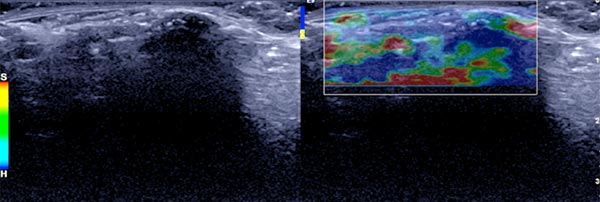

Color-coded duplex sonography also shows total echo reflection. No perfusion detectable even with a very sensitive setting for blood flow (6 cm/s).

In ultrasound elastography, the lesion codes hard (blue) reflecting the high tissue hardness.